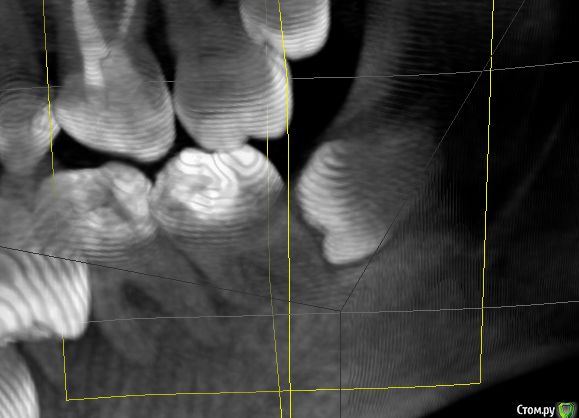

Lewsigh Опубликовано 26 декабря, 2016 Автор Поделиться Опубликовано 26 декабря, 2016 (изменено) Тут наблюдается маленький запас. Но это было три месяца назад. Изменено 26 декабря, 2016 пользователем Lewsigh Ссылка на комментарий